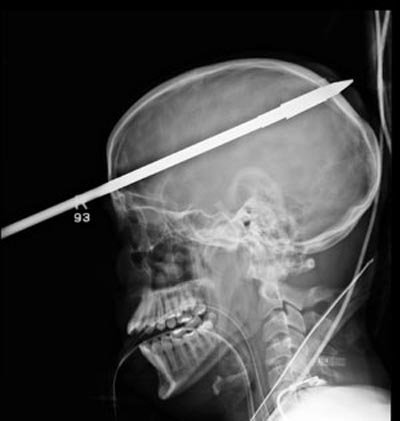

Sau đó, Lopez được trực thăng đưa đến cấp cứu tại Trung tâm Chấn thương Ryder (Bệnh viện Jackson Memorial). Các bác sĩ đã sơ cứu và chụp X-quang vùng đầu. Kết quả cho thấy chiếc xiên đã xuyên thủng hộp sọ và phần não phải của cậu.

Ảnh chụp X-quang cho thấy xiên cá xuyên qua sọ của Lopez. Nguồn: Jackson Memorial Hospital

Các bác sĩ tại Bệnh viện tưởng niệm Jackson tại Miami cho biết mũi tên dài 90cm đã đâm vào trán của Lopez, trên mắt phải 5cm và xuyên qua phía sau đầu.

"Thật là kỳ diệu mũi tên không đâm trúng tất cả các mạch máu chính của não," nhà giải phẫu thần kinh Ross Bullock nói.